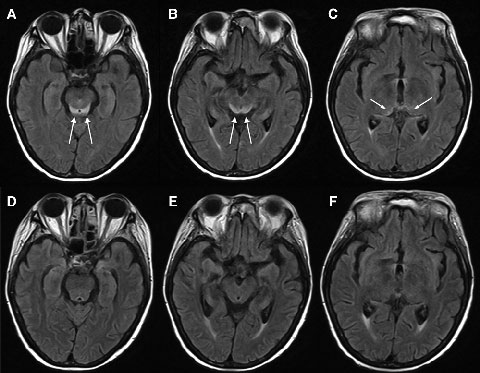

Electroencephalography showed generalised slowing without focal features. Magnetic resonance imaging (MRI) of the patient’s brain revealed symmetrical changes of high signal in the periaqueductal grey matter, superior colliculi and medial thalami, most evident on the fluid-attenuated inversion recovery (FLAIR) sequences (Box 1, A–C). These symmetrical periventricular changes were consistent with typical findings recently described for Wernicke’s encephalopathy.1

Given the clinical history of dietary deprivation and colitis, together with the typical radiological changes, a diagnosis of Wernicke’s encephalopathy was strongly suspected. Hence, intravenous thiamine 500 mg three times a day was administered, after which the patient made a dramatic clinical and radiological recovery (Box 1, D–F) over a period of about 7 days. Despite this, her pretreatment (Day 15) blood thiamine pyrophosphate level, measured using high-performance liquid chromatography, was eventually reported as being normal (136 nmol/L [reference range, 67–200 nmol/L]). However, given her clinical history, the changes noted on MRI and the dramatic improvement in her condition with thiamine, the diagnosis of Wernicke’s encephalopathy remained the most likely explanation.

In the past decade, magnetic resonance imaging (MRI) has been recognised as a useful adjunct in Wernicke’s encephalopathy diagnosis.6 Wernicke’s encephalopathy typically causes symmetrical alterations in MRI signal intensity (increased on fluid-attenuated inversion recovery [FLAIR] images) in the periventricular regions of the brain, including the medial thalami, periaqueductal grey matter, tectal plate (inferior and superior colliculi), and mamillary bodies.1,7 It has been suggested that MRI changes which occur in alcoholic and non-alcoholic patients with Wernicke’s encephalopathy may differ, with contrast enhancement of the mamillary bodies and thalami occurring more frequently in the alcoholic patients, suggesting that these areas may be selectively susceptible to alcohol toxicity.7